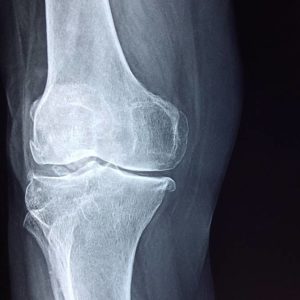

In addition to injuries, there are quite a few joint disorders, such as arthritis, that can be caused or worsened by an injury to the joint. Arthritis is a chronic condition that can gradually get worse over time. While there is no cure, there are treatments available to help manage the pain and inflammation. It’s not uncommon for a patient to have a limited range of motion and chronic pain for the rest of their lives.

Degenerative joint disease is a general term used to describe the gradual deterioration of a joint. This can be caused by many different things, including age, injury, or overuse. As the joint deteriorates, it becomes less stable and more likely to be injured.